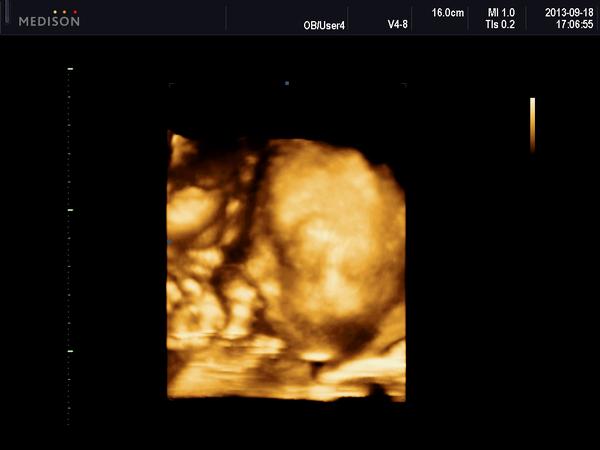

@antana123 jůůůů krásná fotečka 🙂 a s cukrovkou je to pech, ale kamarádka měla u prvního a akorád se trochu omezovala ve sladkém jinak všechno jedla, tak uvidíš 🙂

ve středu jsme byli v poradně já mám těhu cukrovku

mimčo ok a váží 961gramů